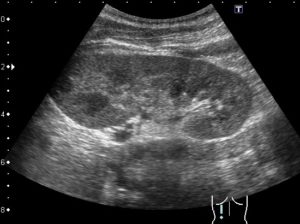

Патологическими считаются и локальные нарушения однородности почечной паренхимы. Вызываются они вследствие роста новообразований и кист.

Однако около 85% всех диагностируемых новообразований почек являются злокачественными. Они склонны к бурному и агрессивному росту, разрушению тканей и изменению размеров органов. Успешность их лечения определяется, прежде всего, ранней диагностикой, а также комплексным подходом.

Ещё одна распространенная причина очаговых изменений структуры паренхимы почек на УЗИ – кисты. Они могут располагаться поодиночке, а также группами по 2-3 и более образований.

Внутри кисты заполнены жидкостью, а диаметр их составляет 3-5 сантиметров. В зависимости от количества подобных элементов, а также от степени сдавления функциональных тканей, выбирается тактика лечения.

Терапия кист проводится как консервативными, так и хирургическими методами.